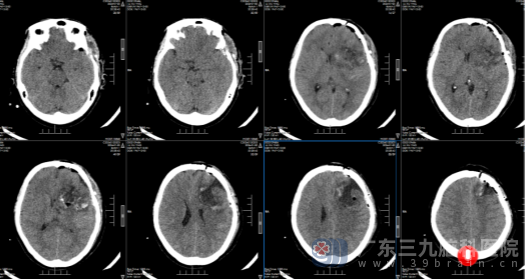

我院神经外十科欧阳辉教授细致阅片后,向家属清晰说明病情:患者左侧额颞岛叶存在大小约54mm×67mm×57mm的肿瘤,左侧额叶部分脑回肿胀,疑似伴脑疝形成,病情危急。结合患者的症状表现与影像学检查结果,科室为卢阿姨完善各项术前相关检查,随后经神经外十科团队集体研讨,明确诊断为左侧额岛叶高级别胶质瘤,制定了精准的手术治疗方案。

影像检查:

术前

术后